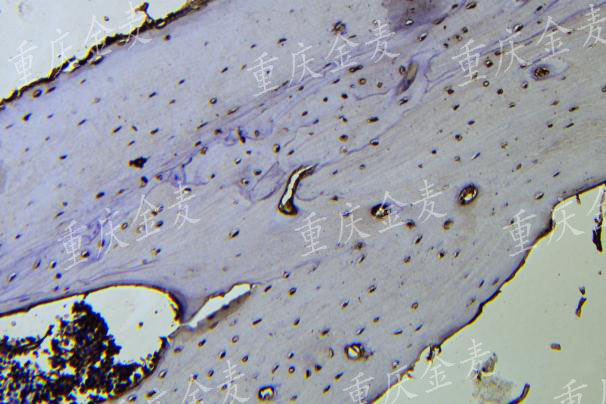

颅骨缺损OCN染色